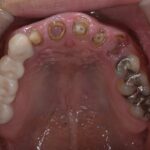

北欧スタイルの歯周治療、予防もふくめ高水準の治療を学べます。